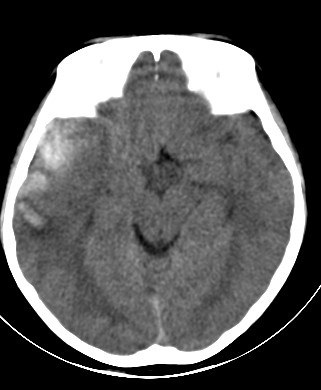

外伤一天,m,21y,骨窗示右颞骨骨折.

请大家看看,是脑内还是脑外(硬膜下还是硬膜外).请说说理由.谢谢.

右侧颞叶大片状形态不规则高密度影,边缘较模糊,无明显白质挤压移位。支持脑错裂伤、脑内血肿。

右侧颞叶大片状形态不规则高密度影,内缘较模糊,外缘紧贴颅板,无明显白质挤压移位伤。

依据:1.右侧颞叶不规则形血肿密度影,周围有水肿;

2.有明显占位效应;

3.颅板下硬膜下间隙存在。

脑内脑外全有,上方比较局限近似梭形改变,考虑硬膜外血肿。没有跨过颅缝,且是脑膜中动脉所在的位置。中线移位,占位效应明显。后方条带状增高影,周围有水肿带,考虑脑内血肿。

右颞叶见混杂密度灶(以高密度灶为主)右侧脑室受压变形,中线结构左移,右颞部颅骨内板下见弧形高密度灶,右侧裂池及部分脑沟内见高密度灶;

结论:1:右颞叶脑挫裂伤;

2:右侧硬膜下血肿;

3:蛛网膜下腔出血。